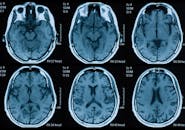

- Neuro-Optometry

Papilledema Associated With Meningioma

Foville Syndrome Associated With Cerebellar Arteriovenous Malformation Resection